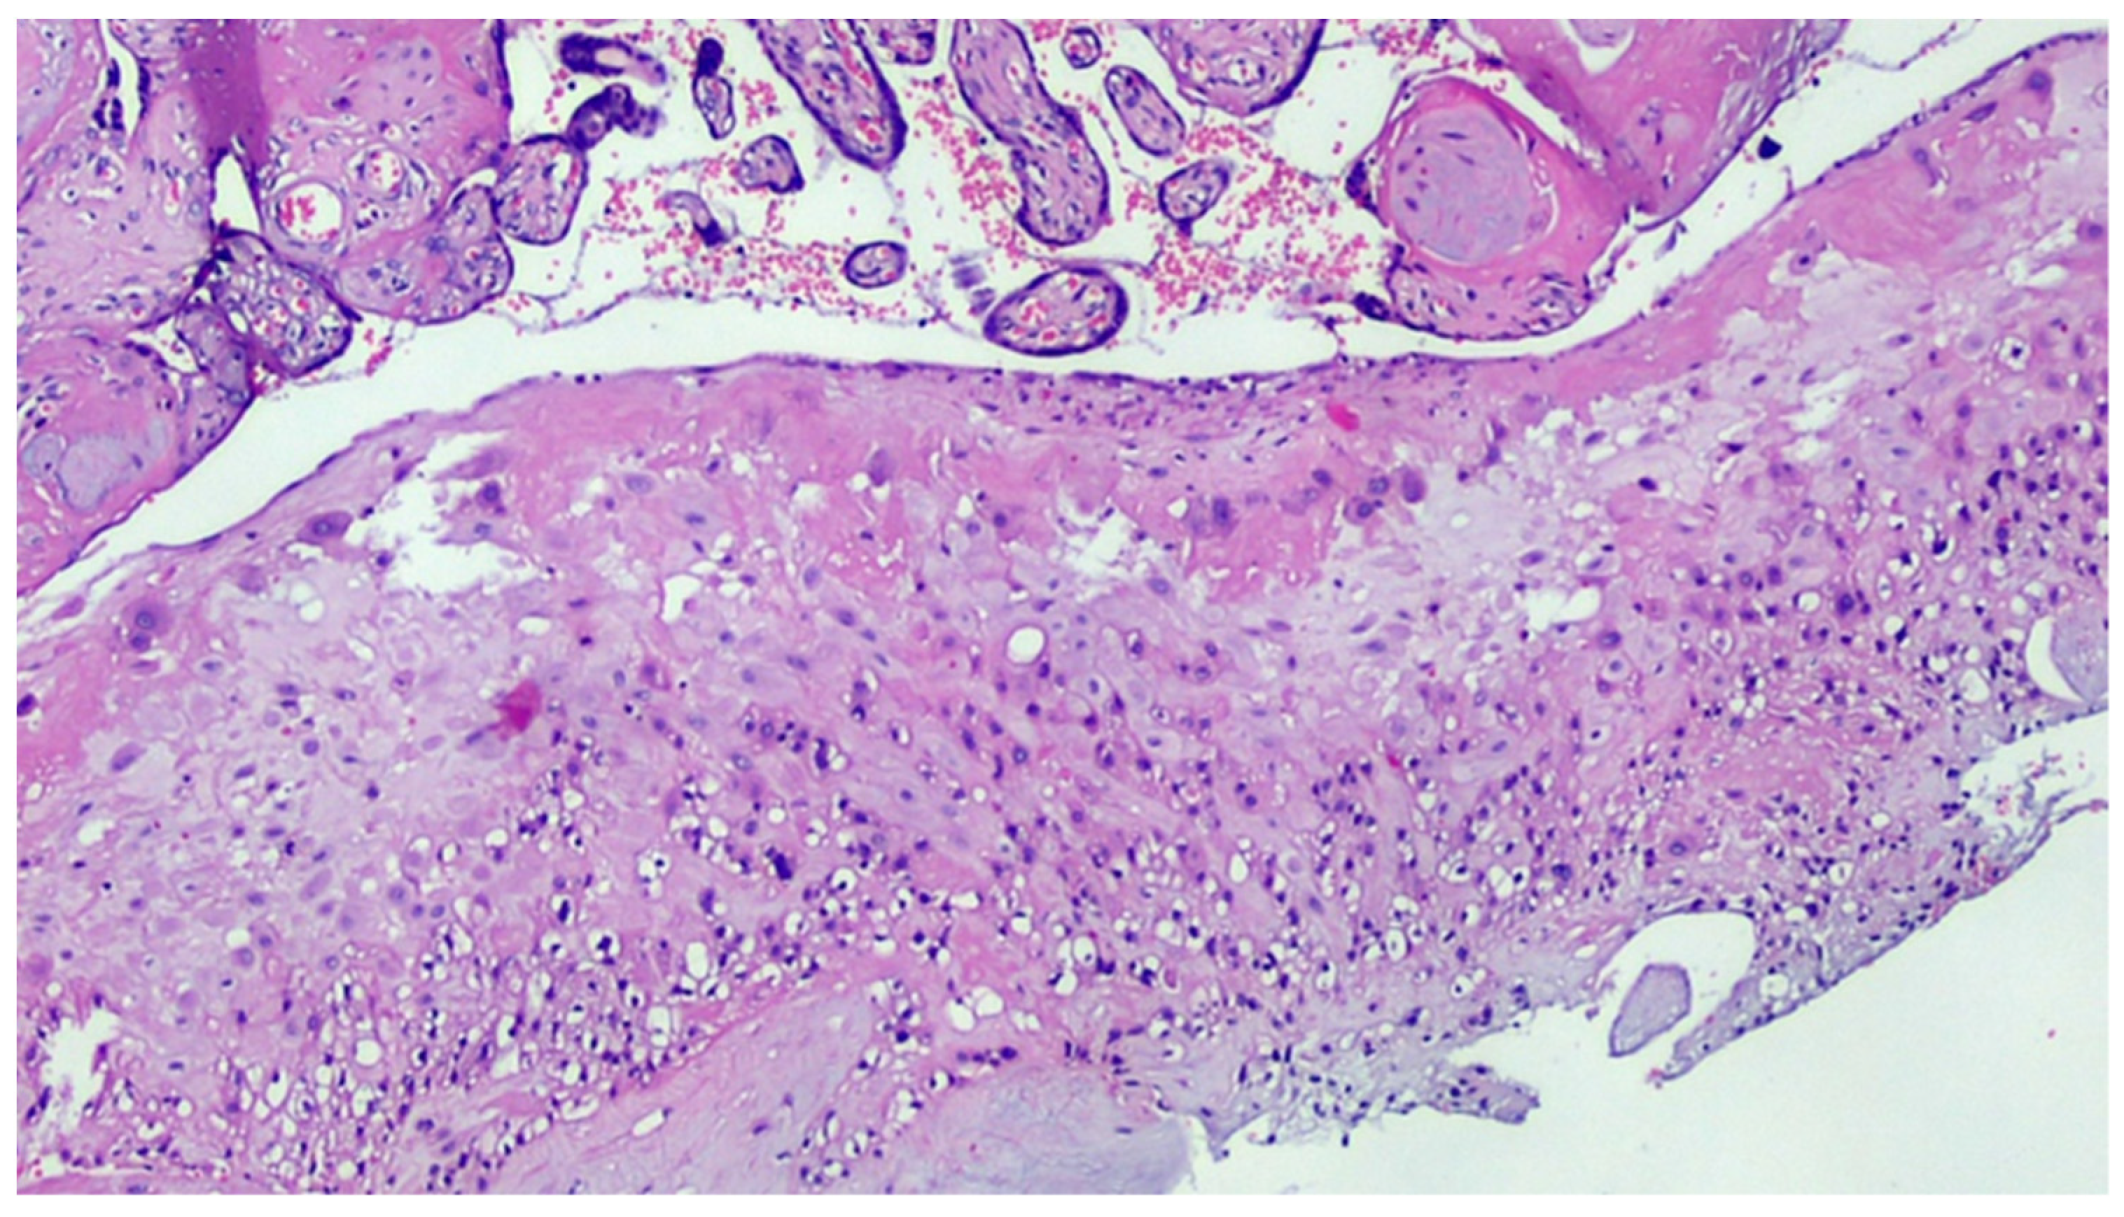

Figure 4.

Deciduitis with large foci of necrosis and massive infiltration of mainly granulocytic inflammatory elements (acute deciduous, H&E, 200×) in the placenta of a COVID-positive mother.